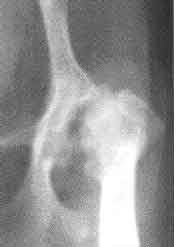

Radiographic (X ray) signs of Legg Perthes are usually gross and discouraging, since many cases are not referred to the vet or the specialist for diagnosis until the dog has been limping for a long time or the disease has progressed to the point that it becomes a more real problem to the owner. These small dogs put so little weight on their tiny hip joints that they almost can compensate for discomfort by “walking on their forelimbs instead of their four limbs.” Many are “couch potatoes” or spend much time being carried, but even then, picking up an affected dog in a certain manner can put more pressure on the joint than normal locomotion, so pain at that time is often the stimulus to do something about it. Owners and vets have reported “incredible pain” and constant, progressive discomfort, inability to stay long in any one position, and bone lysis (loss through a process akin to dissolving or consuming) at other areas in the limb distal (further away, the opposite of proximal) to the hip.

These are similar to those in LCPD. The earliest radiographic signs of LCPD, should you look for them before they change, include an increased radiodensity (opacity as seen on the radiograph) in the lateral part of the epiphysis of the femoral head. Lateral means the part away from the mid-line or medial; the “outside.” Resorption of necrotic (dying, rotting or decomposing) trabecular bone cells is next, accompanied by a lysis (dissolving or being consumed) of bone. These are replacement attempts by the body, similar to the attempt to replace bone that takes place during HD remodeling; eventually there is fracture or collapse, like a frame house riddled by termites. As HD may or may not be concurrent, the congruity of the ball and socket coxofemoral joint might still be maintained until collapse.

Some cases of Legg-Perthes go unreported or misdiagnosed. And some of us may not have heard of any of our specific breeds diagnosed with Legg-Perthes yet, because, to some veterinarians, the radiograph looks like hip dysplasia, and it is not sent in to OFA, or PennHIP for diagnosis and recording of data. I have seen a few cases misdiagnosed by local vets. If you come across a confirmed case of Legg Perthes in your non-toy breed, please report it (accurately, with name and address of person diagnosing it) to the health committee and/or magazine editor of your breed club.

| Legg-Perthes is mostly found in Toy breeds. | Legg-Perthes; showing necrotic femoral head | Legg-Perthes necrosis with HD |